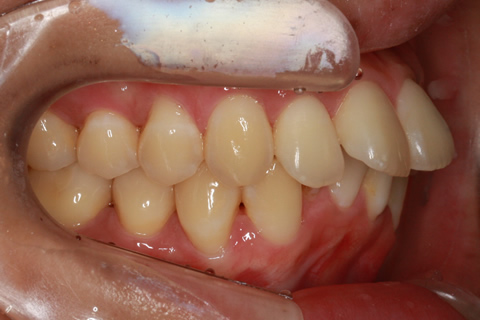

ハーフリンガル矯正2:上の歯のみ舌側矯正で治療(矯正期間18ヶ月)

- 年齢・性別

- 23歳女性

- 治療期間

- 1年6ヶ月

- 抜歯

- 上顎4番

- 治療費

- 110万円(税込み)

- 備考

- ハーフリンガル矯正

- 治療内容

- 上下前歯部凸凹の改善

- 施術の副作用(リスク)

- 裏側矯正の特性上、表側矯正と比較すると治療期間が長くかかる場合が多い。